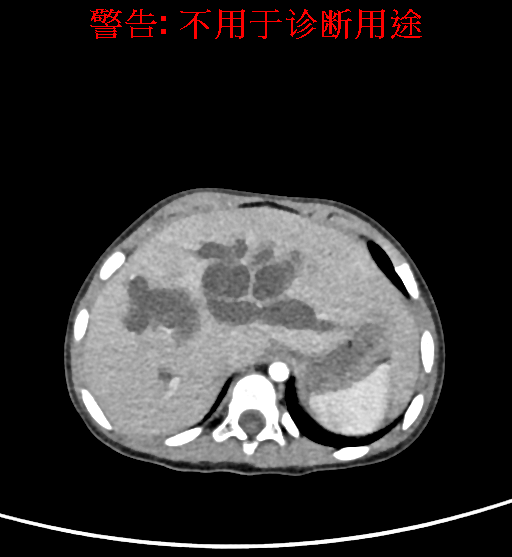

实验室检查: 血常规:血常规:WBC 11.49*109/L,NEU3.60*109/L,RBC4.36*1012/L,HB 119g/L, PLT 411*109/L,MCHC 318.0g/L, PCT 0.45%, RET% 1.64% 生化全套:ALT 18.00 U/L, AST 44.00 U/L, ALT/AST 0.41, ALB 47.35g/L,BIL-T 6.60 umol/L, BIT-D 2.68 umol/L, BUN 4.80 mmol/L, CREA 18.00 umol/L 肝炎全套: 炎症反应标志物: 诊疗过程: CT结果输入海信CAS系统后行3D重建及手术规划后,于2018-6-7全麻下行“胆囊切除+胆总管囊肿切除+肝总管空肠吻合术”手术治疗: 术前三维重建及手术方案设计: 将0.625mm双源薄层CT资料的静脉期和动脉期Dicom格式文件导入海信CAS系统。 通过调节窗宽窗位调整CT序号,对肝实质,胆囊,下腔静脉,肿瘤,肝动脉、门静脉及肝静脉等进行三维重建;系统自动计算肝脏体积,肝脏体积为383.8ml,通过术前模拟手术,精准判断手术切除范围,进行精密术前规划及讨论后实施手术。 手术步骤: 麻醉成功后,患儿取平卧位,2.5%碘伏消毒手术区皮肤,铺无菌巾单。取右上腹纵口长约5m,切开皮肤、皮下织组,腹直肌前鞘、腹直肌,后鞘和腹膜。探查见:胆总管3×2cm大小,胆囊管迂曲,长约10cm。剥离、切除胆囊,游离胆总管,将之横断:①近端即肝总管,剪裁后被吻合用;②远端游离切除囊肿内壁,直至胆总管开口于十二指肠处,冲洗后予以结扎缝扎。距treits韧带20cm处横断空肠:①近端与其远端25cm处的空肠侧壁行端侧双层吻合,吻合口通畅;②远端断端封闭,其侧壁剪开,并经横结肠后提至肝门处,与剪裁的肝总管行端侧双层吻合。缝合修补胆囊床及系膜裂孔,肝门部放置橡胶引流管一根。温盐水冲洗腹腔。检查无活动性出血,清点纱布器械无误,依次缝合腹壁各层。手术顺利,麻醉满意,出血不多,未输血,术后病人先进入麻醉恢复室,苏醒后回病房。手术时术者可开启Hisense CAS系统手势控制功能,对肝脏及胆囊解剖结构进行实时、全方观察、评估,起到术中导航作用。 术后病理: 1. (囊肿壁)囊肿性病变,囊壁构成于增生的纤维组织呈慢性炎,内衬假复层柱状上皮,囊壁内见较多增生的腺体。请结合临床。 2. 慢性胆囊炎。 随访情况: 患儿术后2周恢复良好 术前CT检查:动脉期

静脉期